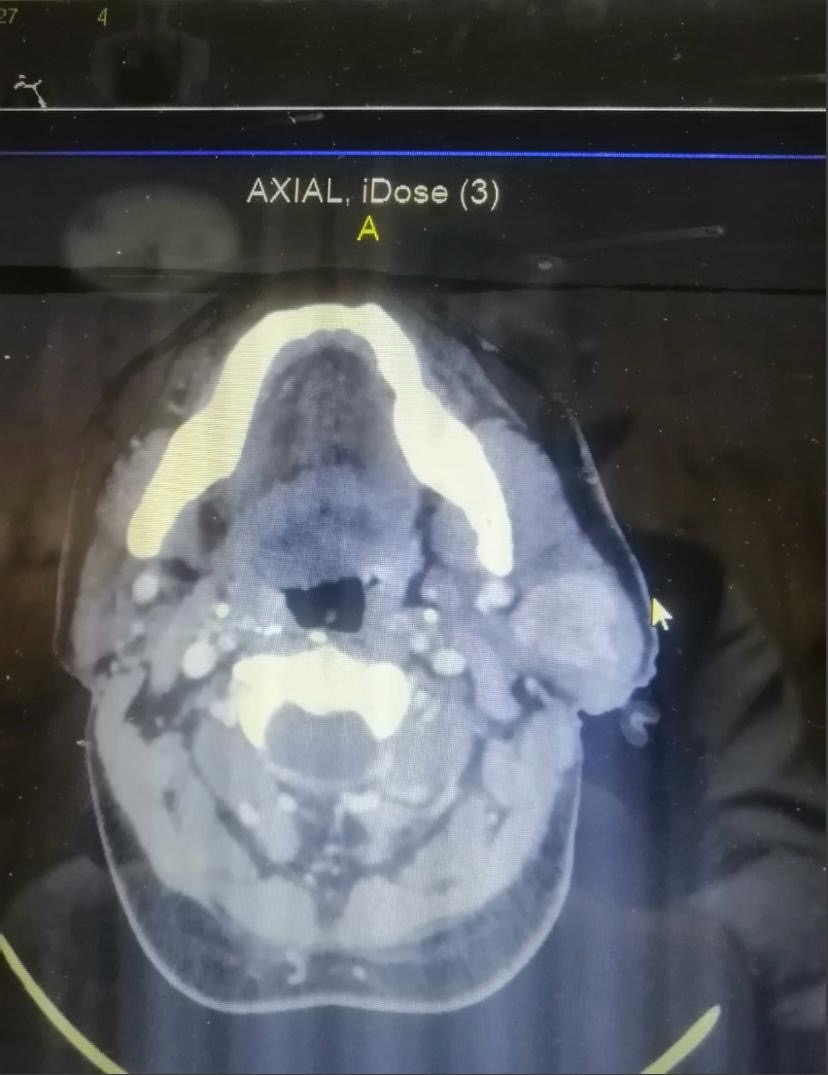

قام فريق طبي متخصص بالمستشفى الميداني الأردني نابلس/١ من إجراء عملية جراحية لاستئصال ورم بالغدة اللعابية.وقال قائد المستشفى: "إن العملية قام بها فريق طبي متخصص وفنيي عمليات وتخدير، وتأتي في إطار الجهود والخدمات الطبية والعلاجية التي يقدمها المستشفى من أجل مداواة المرضى من الأهل في فلسطين، مبيناً أنه تم إجراء العملية بنجاح وتماثل المريض للشفاء. وبين أخصائي جراحة الوجه والفكين بأن المريض الذي يبلغ من العمر (٥٠) عام كان يعاني من انتفاخ وتورم بمنطقة الوجه والرقبة، وبعد الفحص السريري والإشعاعي تبين وجود ورم ليمفي غير سرطاني بالغدة النكافية،وأوضح أخصائي التخدير والعناية بأن مثل هذه الحالات والتي تتم تحت التخدير الكامل، يتعين إجراء الفحوصات اللازمة التي تؤكد سلامة المريض أثناء العملية وبعدها.وعبر ذوو المريض عن بالغ شكرهم وتقديرهم لجلالة الملك عبد الله الثاني ولجهود طواقم المستشفى الميداني لإجرائهم العملية، وما يقدمه المستشفى من خدمات ساهمت في إثراء الخدمة الصحية المقدمة للمجتمع المحلي في نابلس في ظل الظروف الراهنة.